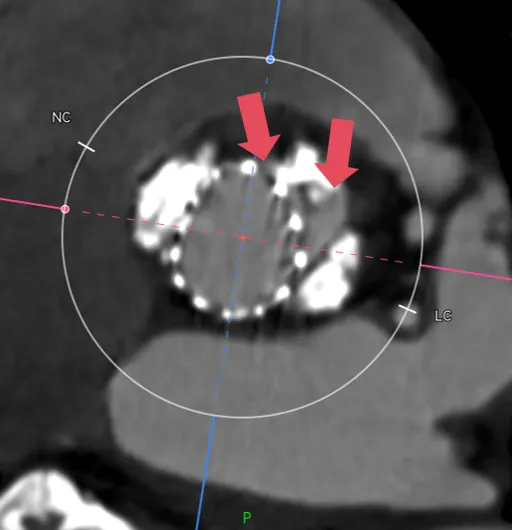

再一个例子,病例-7,这个更明显了,可以看到虚拟的地方有一半的空隙。

这种病例你想要怎么实现良好的封堵呢?那一定是要在这个地方有覆膜区,而且可以完全贴上,一个层面一个层面看,可以发现找不到一个层面没有空隙的。

这个时候就要预估病人的术后瓣周漏风险了,需不需要一起放个封堵器,箭头指的地方都是导致PVL的地方。